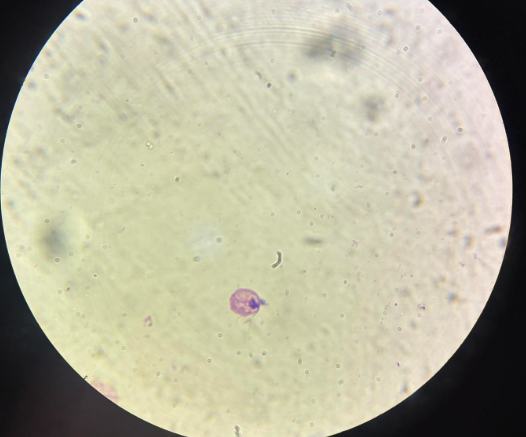

plasmodium falciparum stadia schizogonii krwinkowej

plasmodium falciparum stadia schizogonii krwinkowej

plasmodium ovale stadia schizogonii krwinkowej

plasmodium ovale stadia schizogonii krwinkowej

babesia sp stadia schizogonii krwinkowej

babesia sp stadia schizogonii krwinkowej